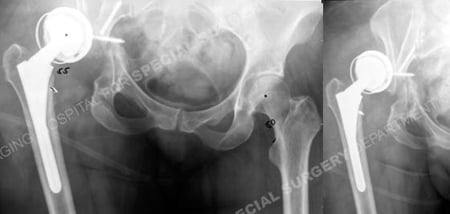

Anteroposterior radiographs revealing a periprosthetic acetabular with an anterior dislocation.